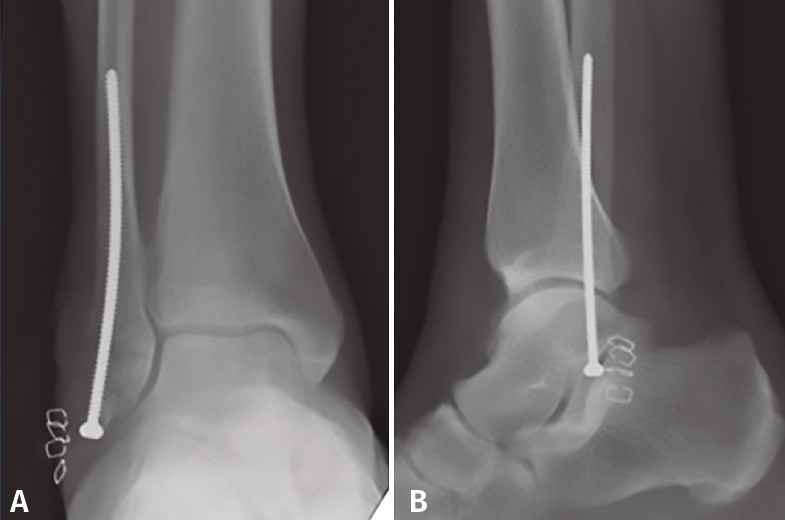

La osteosíntesis endomedular del peroné está descrita con diferentes tipos de tornillos, siendo los más utilizados en la literatura los tornillos de 3,5, 4,2 o 4,5 mm(17). Nuestra preferencia personal es la utilización de un tornillo cortical de 3,5 mm largo, de 80 a 120 mm de longitud (de la caja de pelvis), debido a la mayor flexibilidad del implante y la capacidad de adaptación al canal medular(52,55)(Figura 4). Este tornillo puede permitir incluso la reducción del desplazamiento lateral del fragmento distal del peroné con el punto de entrada adecuado en la punta del peroné(55). Esta técnica también permite espacio para añadir un tornillo para la estabilización de la sindesmosis(17,53).

Figura 4. Tornillo intramedular de peroné (cortical de 3,5 mm). Nótese la flexibilidad del tornillo y la capacidad de adaptación a la cavidad medular.